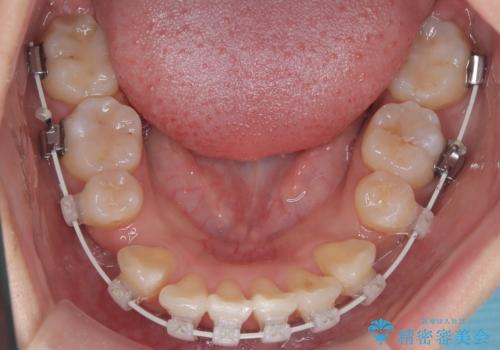

今回の矯正治療では、まず計画通り上下左右の小臼歯4本を抜歯し、八重歯や正中のズレを解消するための十分なスペースを確保しました。装置には、目立ちにくい白いブラケットとワイヤーを使用した審美ワイヤー矯正を採用。

抜歯によってできたスペースを利用し、

八重歯: 突出していた八重歯を歯列内に誘導し、デコボコを解消しました。

正中のズレ: 歯を左右対称に移動させることで、上下の歯の中心線を正確に合わせ、顔全体のバランスも改善しました。

治療の結果、長年気にされていた八重歯と正中のズレが解消し、機能的にも整った理想的な歯並びを獲得。目立たない装置で治療を完遂し、自信を持って笑える美しい笑顔を手に入れていただけました。